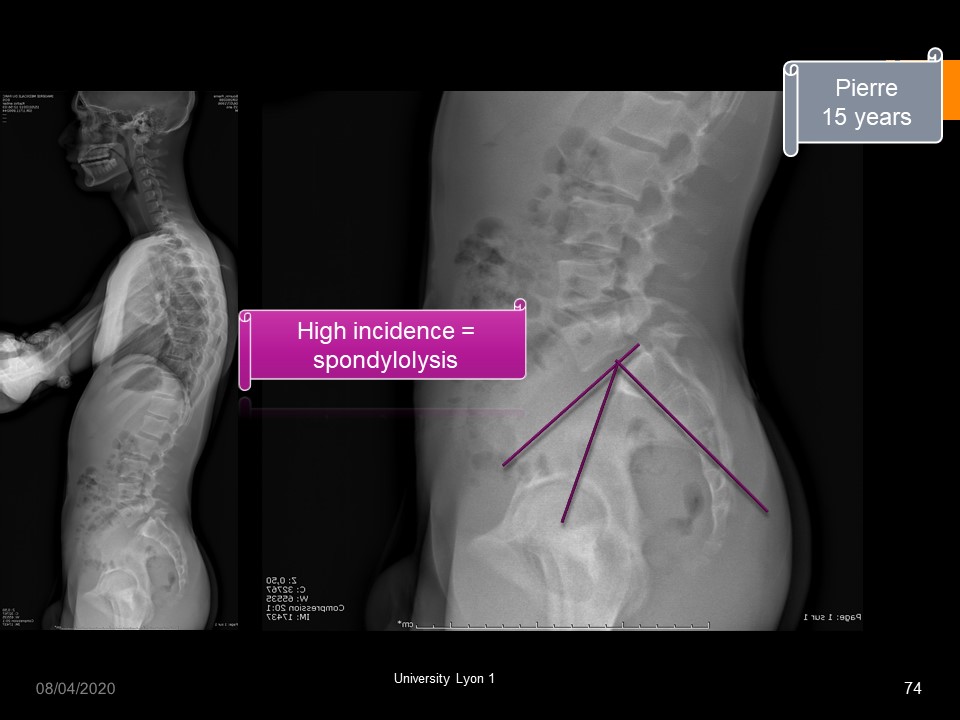

The fracture of the posterior arch of L5 is very frequent among homo sapiens, with however differences according to the origin of the population. It is very common (30 to 60%) among the Inuit who have a specific genetic sequence that allows them to resist at the cold. (Denisov’s man).

The upper facet joint is subjected to forward sliding stress. The lower facet joint is subject to sliding stress up and back. Spondylolysis affects 5 to 7% of the Caucasian population.

The epidemiology was well specified by Rossi in 1995. It does not exist at the time of birth. The mode of transmission is dominant with reduced penetrance. It concerns 25% of athletes. The location is L5 in 95% of cases and bilateral in 95%.

Spondylolysis with high incidence. In this case hyperkyphosis is associated.